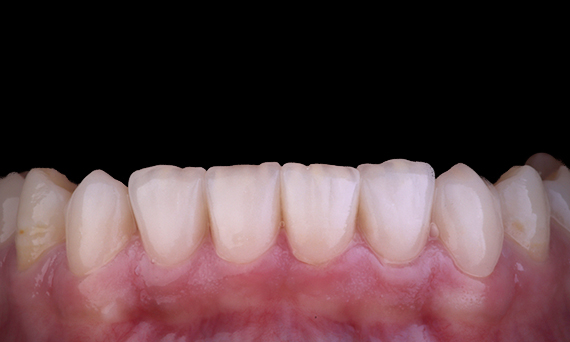

El paciente presentaba periodontitis apical asintomática en el diente 34. En la radiografía preoperatoria, se observó el diente 34 con dos raíces visibles. Sin embargo, los datos del CBCT confirmaron un premolar de tres raíces y los canales divididos en tres en la raíz media. Una selección cuidadosa de la lima es fundamental para este diente delicado.

Dr. Jack Lin, endodoncista, Sídney, Nueva Gales del Sur, Australia

En esta situación, la preservación de la estructura del diente y la raíz es esencial para reducir el riesgo de desplazamiento, transporte, compresión, perforación y fractura de la raíz. La selección de casos, el diagnóstico y la planificación previa al tratamiento son muy importantes. Es fundamental la selección de limas de endodoncia con flexibilidad, eficiencia y respeto por la anatomía natural de la raíz.